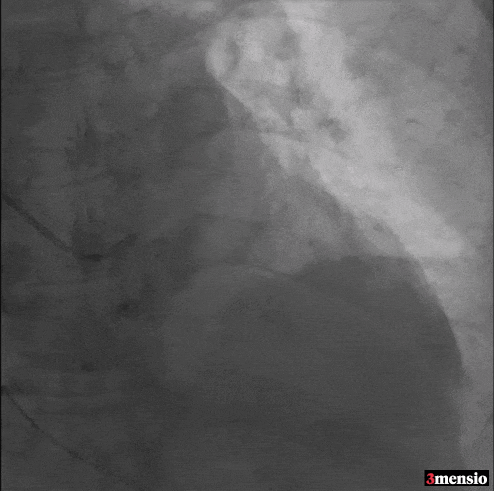

心脏超声

患者为Type1带嵴二叶瓣,存在室间隔膜部瘤,左右融合嵴伴钙化,瓣叶增厚。

该患者存在起源于瓣环下的室间隔膜部瘤,该瘤体上缘延伸至瓣环上方7.2毫米(图B)。

回顾经胸超声心动图图像时,观察到左心室与主动脉瓣上之间可能存在交通。

为了更深入地理解此例二叶式主动脉瓣的解剖结构,评估解剖瓣环径线,在瓣环上方进行了多平面测量。